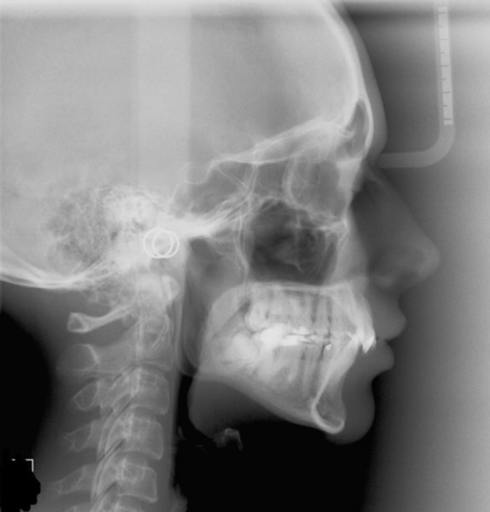

In this image of my condyles, do they appear normal/healthy or is there any bone loss?

Attached is an image of my condyles. Are they normal and healthy or Do you see any bone loss such as flattening or erosion of them? If there does appear to be some bone loss, how does this affect my bite and the appearance/position of my jaw?? Is...